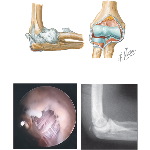

Condtions In the Tendons of the Elbow